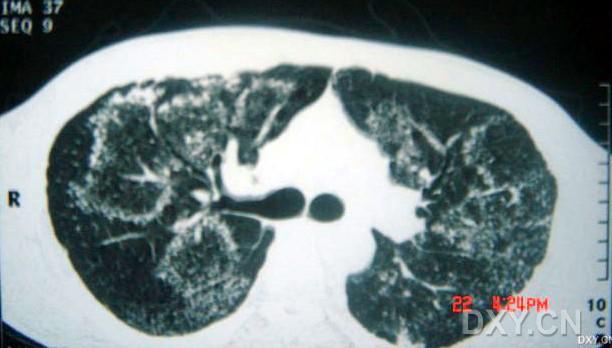

影像表現(xiàn):

兩肺彌漫性顆粒狀陰影,部分陰影融合呈團塊狀,可見支氣管氣相;

呈非對稱,非均勻分布性,部分肺野呈磨玻璃密度;

多處胸膜局限性增厚,胸水征(--)縱隔窗為正常。

臨床表現(xiàn)提示為非細菌性感染性疾病,ct表現(xiàn)為以肺泡實變?yōu)橹鞯膹浡躁幱埃?/font>

病理結(jié)果為:過敏性肺泡炎。